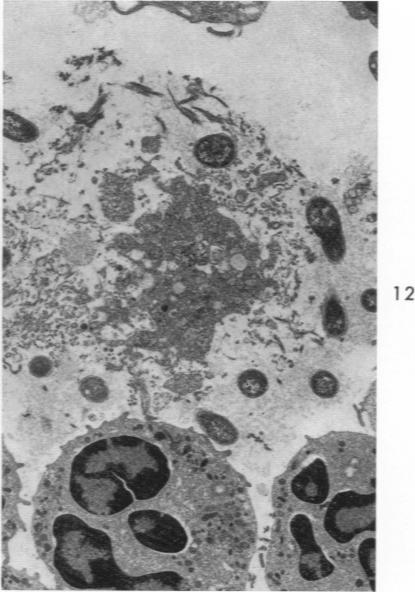

Pneumonic plague in monkeys. An electron microscopic study.

Am J Pathol. 1969 Feb;54(2):167-85.